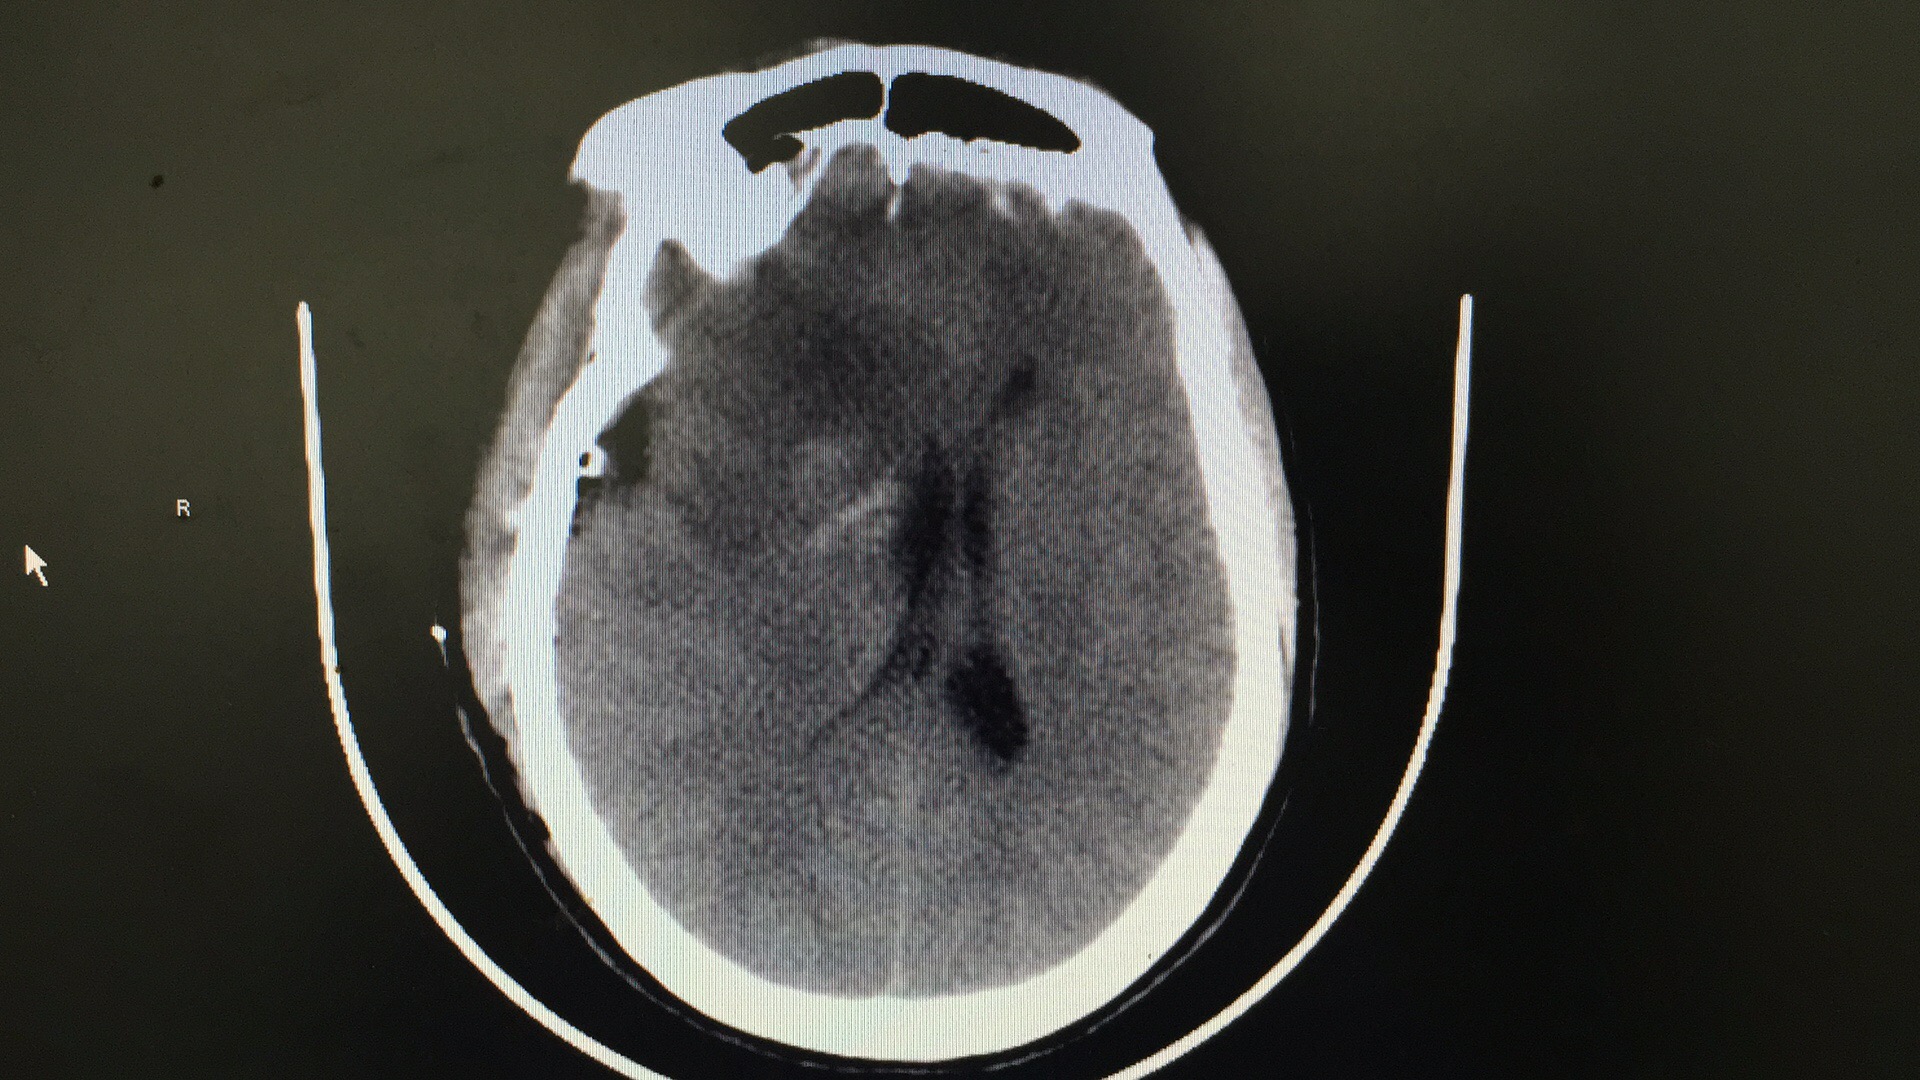

病人术后片